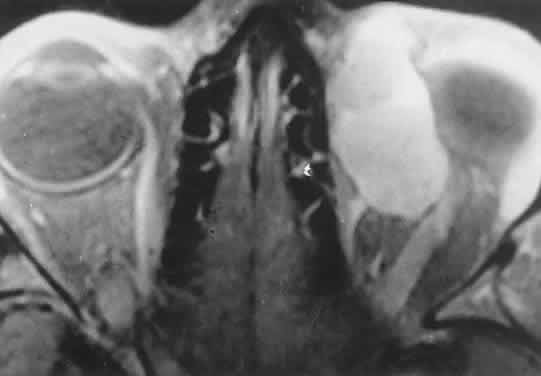

Orbital myositis may represent a greater proportion of cases of IIPT in childhood than in adulthood, and involvement of multiple extraocular muscles may occur more frequently in children than inadults. In orbital myositis, early diplopia and increased discomfort with attempted eye movement are typical symptoms. CT may show enlargement of one or more extraocular muscles in one or both orbits (Figs. 21 and 22). When a single muscle is involved, the specter of a primary or metastatic neoplasm within the muscle may be raised. However, external inflammatory signs, considerable pain and limited motility, and an explosive onset of symptoms within 24 hours all suggest orbital myositis. The uniform enlargement of the muscle, including its tendinous insertion (see Fig. 22), also helps distinguish the process from a neoplasm, which might be expected to produce a more focal, globular expansion. Echography may support the diagnosis of inflammation by showing edema in the episcleral space as a relative sonolucency between the scleral and orbital fat echoes (Fig. 23). Its CT counterpart is an increase in the radiodensity and thickness of the ocular tunica.

Fig. 21. A. This 16-year-old boy had acute onset of bilateral proptosis, pain, diplopia, chemosis, and conjunctival injection. B. Bilateral enlargement of the superior and medial rectus and inferior oblique muscles. Other sections showed similar involvement of other extraocular muscles.

Fig. 22. The uniform enlargement of the left medial rectus muscle, including its tendinous insertion, is characteristic of orbital myositis.

Fig. 23. Acoustic discontinuity between the globe and the orbital fat indicates inflammatory edema in Tenon's space.